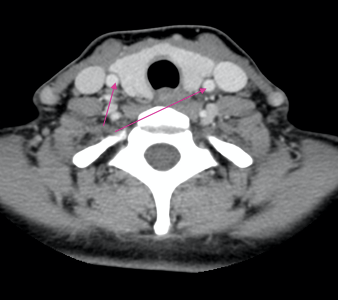

What is indicated by the arrows?

Common carotid arteries